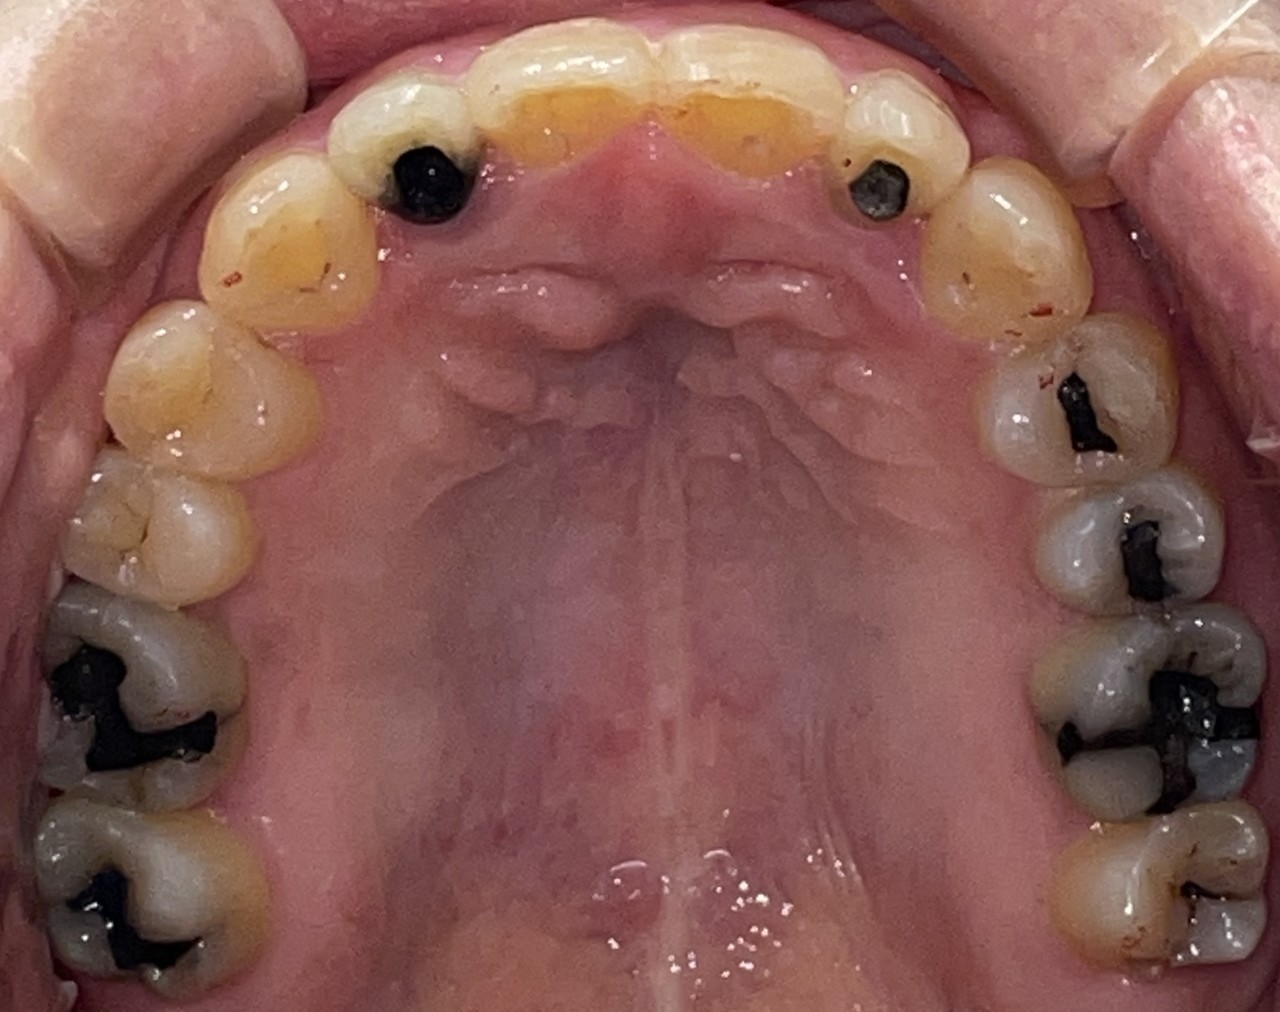

Before

After

矯正の種類 / invisalign GO

年齢・性別 / 30代女性

主訴  /  叢生 かみ合わせ

治療期間 / 17ヶ月

費用 / 簡易検査 5,000円(税別) 精密検査 30,000円(税別)

両額マウスピース 450,000円(税別)  両額リテイナー料 60,000円(税別)

※マウスピース交換時別途調節料3,000円(税別)

副作用 / 口内炎・歯の移動に伴う痛み・知覚過敏 ※数日で収まる場合が多いです

リスク / 後戻り防止の為、夜のみマウスピースで保定を指示